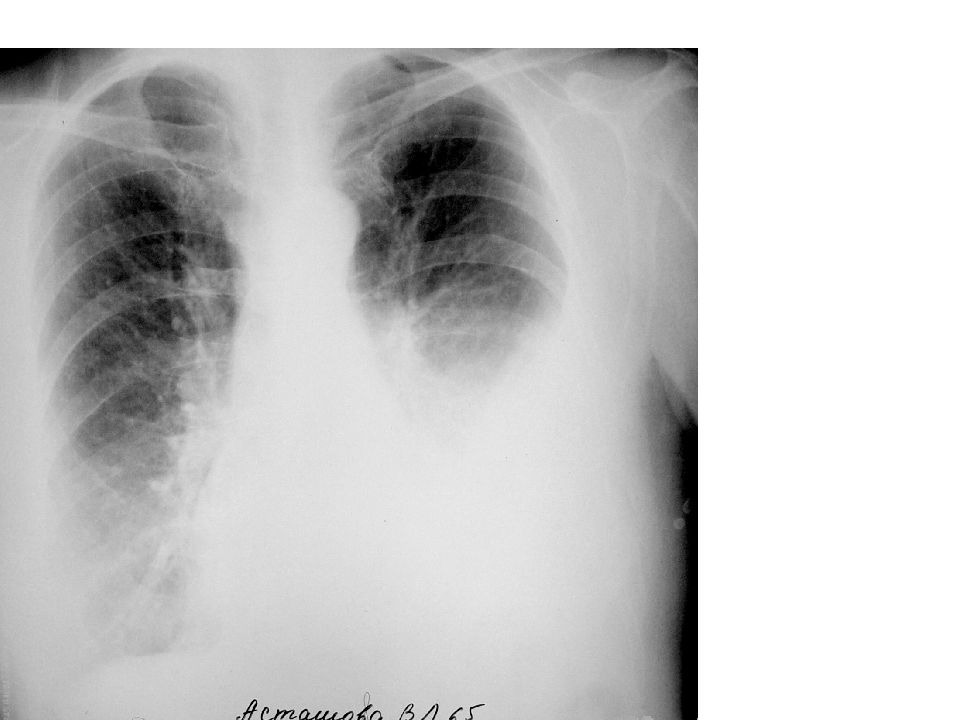

Рентгеновские снимки опухоли Панкоста